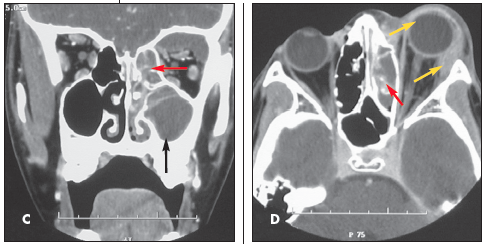

Intraorbital abscess: The radiographs demonstrate opacity of the ethmoid air cells on the left (A and B, blackarrows) with increased opacity of the left maxillary antrum, which is best seen on the frontal view (A, red arrow). The sphenoid and frontal sinuses are unremarkable. The increased density seen on the films results from the filling of the normally aerated sinuses with opaque material (in this case, mucus).

Close inspection also reveals increased density of the left orbit (A, yellow arrow). This density is attributable to edema.

Coronal (C) and axial (D) CT images confirm the radiographic findings of opacity of the ethmoid air cells (red arrows) and maxillary antrum (black arrow) caused by mucus and fluid. These images also define the extent of orbital edema and proptosis (yellow arrows).